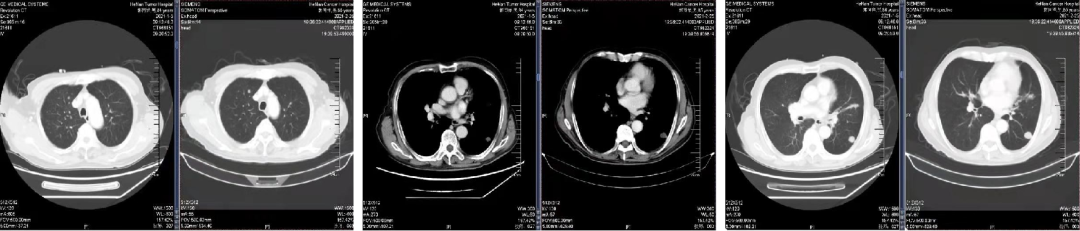

02 初诊病史

诊断:直肠腺癌双肺转移IV期,KRAS 突变型,MSS。高龄,患者及家属无手术意愿,全身系统治疗。

03 治疗方案:全身系统治疗

一线治疗

2021.01.14 始行“卡培他滨”方案化疗2周期。

二线治疗

于2021.03.02、2021.03.24 行“卡培他滨+贝伐珠单抗”方案化疗2周期。

三线治疗

于2021.04.14 始行“曲氟尿苷替匹嘧啶片(TAS-102)+贝伐珠单抗”2周方案治疗至今。

04 疗效评估

患者疾病控制良好,耐受情况好。